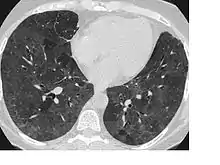

CT showing diffuse ground-glass opacities in periphery of both lungs in patient with COVID-19.

Ground-glass opacity is among the most common imaging findings in patients with confirmed COVID-19.[17][18] One systematic review found that among patients with COVID-19 and abnormal lung findings on CT, greater than 80% had GGOs, with greater than 50% having mixed GGOs and consolidation.[17] GGOs with mixed consolidation has most often been found in elderly populations.[19] Several studies have described a pattern among initial, intermediate, and hospital discharge imaging findings in the disease course of COVID-19. Most commonly, initial CT imaging reveals bilateral GGOs at the periphery of the lungs. During initial stages, this is most often found in the lower lobes, although involvement of the upper lobes and right middle lobe has also been reported early in the disease course.[17][19] This is in contrast to the two similar coronaviruses, SARS and MERS, which more commonly involve only one lung on initial imaging.[20][21] As the COVID-19 infection progresses, GGOs typically become more diffuse and often progress to consolidation.[12][19] This is sometimes accompanied by the development of a crazy paving pattern and interlobular septal thickening.[19] In many cases the most severe pulmonary CT abnormalities occurred within 2 weeks after symptoms began.[18] At this point, many individuals begin showing resolution of consolidation and GGOs as symptoms improve. However, some patients have worsening symptoms and imaging findings, with further increase in septal thickening, GGOs, and consolidation. These patients may develop lung "white-out" with progression to acute respiratory distress syndrome (ARDS) requiring treatment escalation.[18][22]